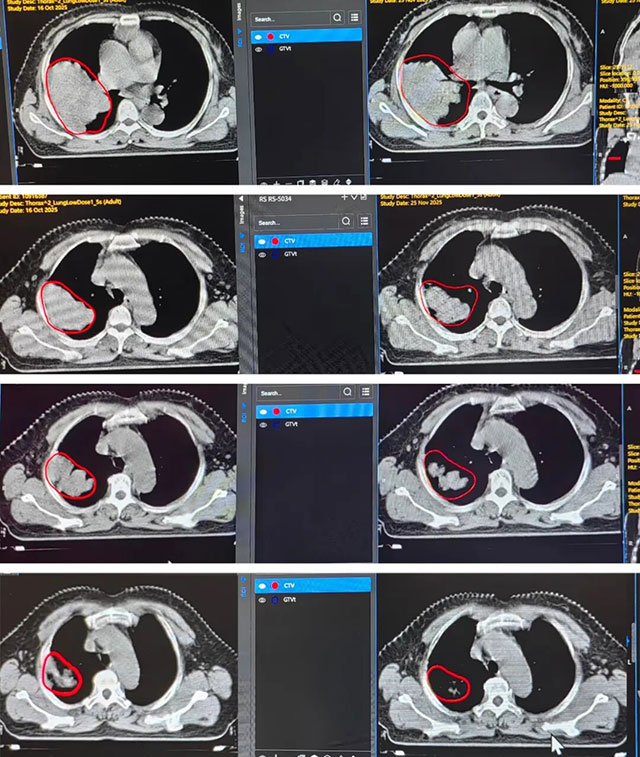

技术核心:张燕团队没有选择常规的“大剂量强攻”,而是通过CT精准定位,将射线聚焦右肺病灶,巧妙避开纵隔、胸膜等正常组织。针对治疗中出现的骨髓抑制,同步给予升血小板、升粒细胞支持。

诊断:左肺鳞癌(cT4N2M0 IIIB期),侵犯纵隔大血管

陈先生的肿瘤长得像一朵巨大的“菊花”,形态极不规则,分叶丛生,死死地包绕着左肺门大血管,并且免疫组化显示Ki-67高达60%+(意味着肿瘤生长极快,极具侵袭性)。剧烈的咳嗽让他夜不能寐。面对这种“贴着血管长”的肿瘤,放疗稍有不慎就可能导致大出血。

技术核心:张燕团队创新性地采用了“周边低剂量结合肿瘤中心空间排布高剂量点照射”的模式,产生旁观者效应,有效激活免疫反应。同时,针对化疗后的恶心呕吐,同步给予护胃、止吐干预。